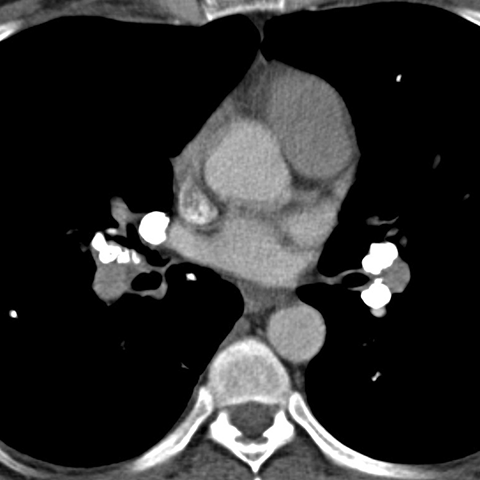

Calcified Hilar Nodes, Remote Granulomatous Infection [3 of 4]